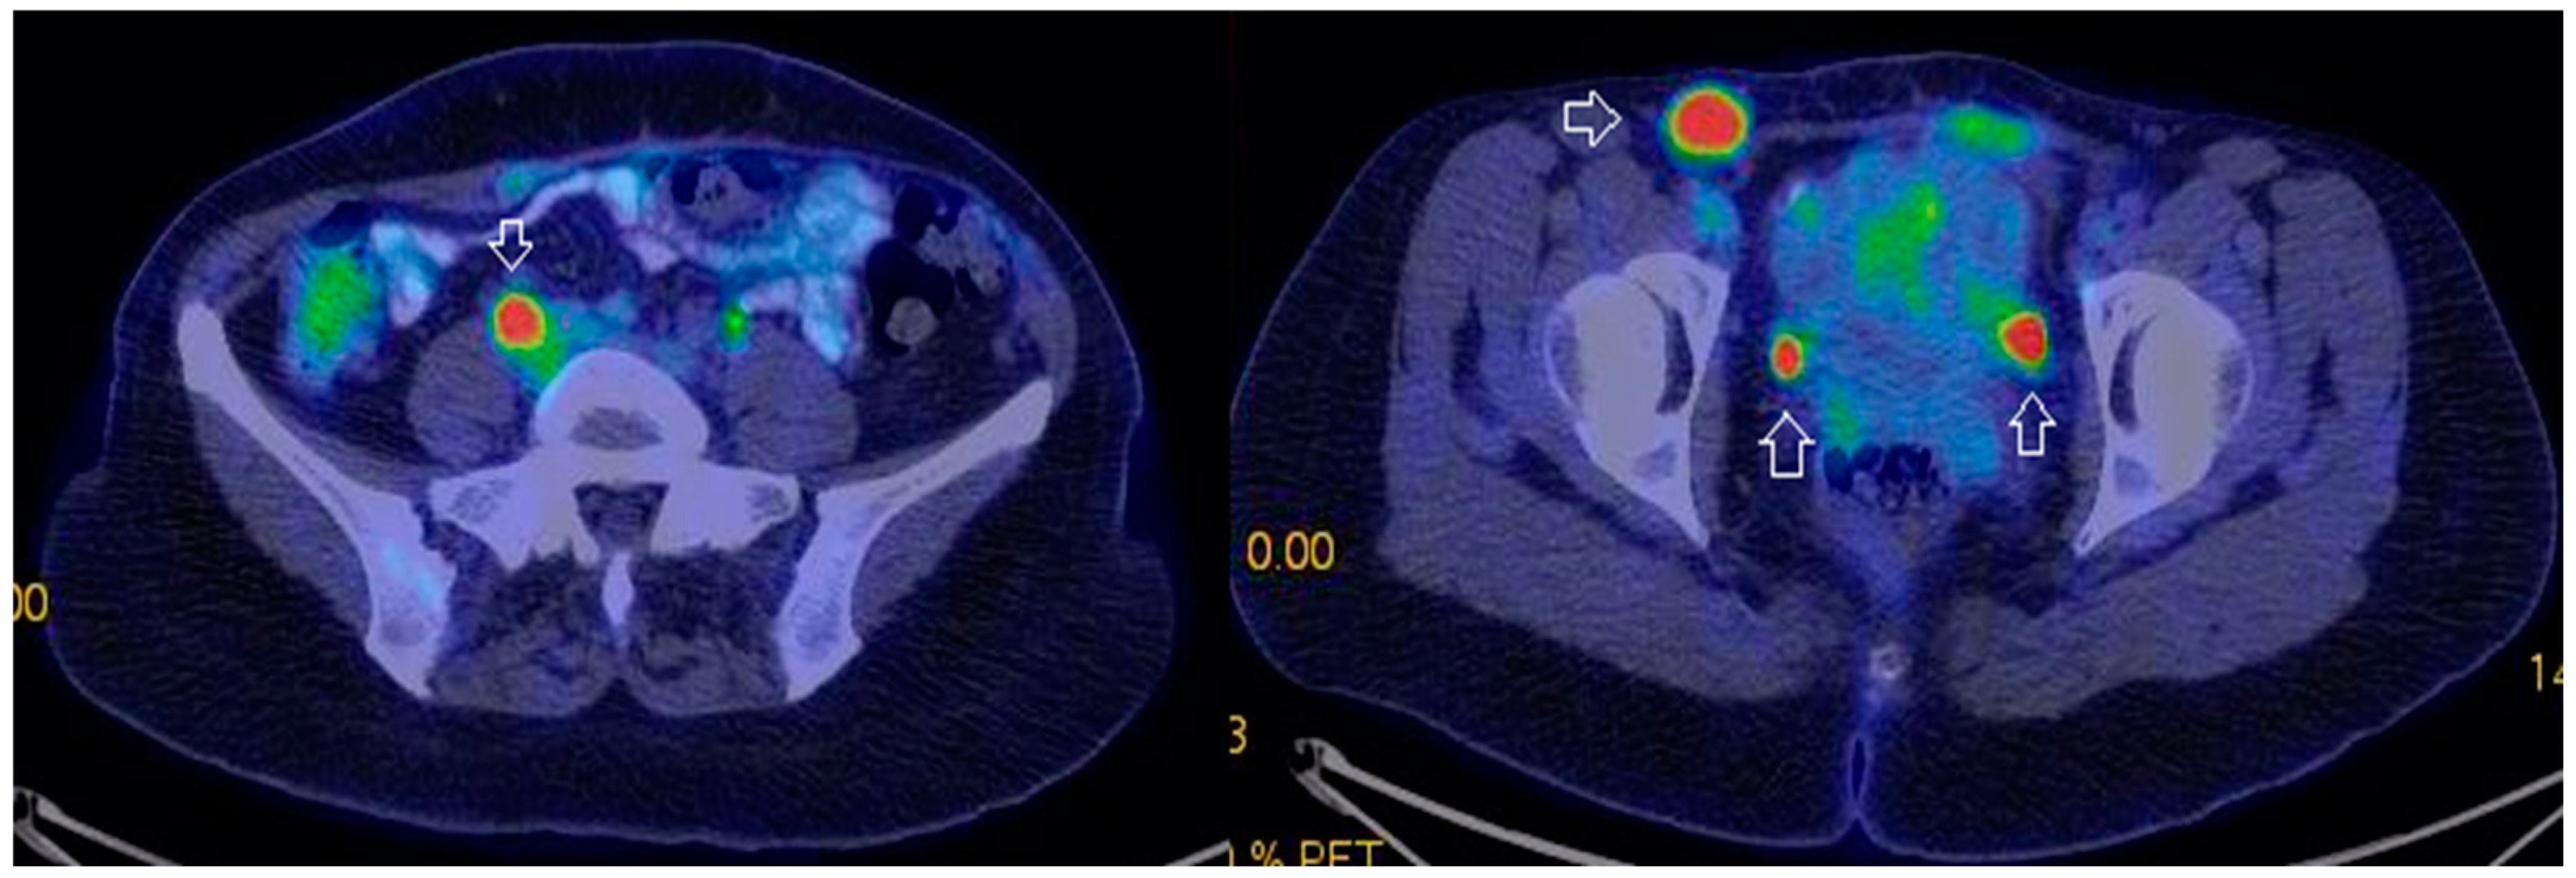

- Tardieu, A.; Ouldamer, L.; Margueritte, F.; Rossard, L.; Lacorre, A.; Bourdel, N.; Lades, G.; Sallée, C.; Monteil, J.; Gauthier, T. Assessment of Lymph Node Involvement with PET-CT in Advanced Epithelial Ovarian Cancer. A FRANCOGYN Group Study. J. Clin. Med. 2021, 10, 602. [Google Scholar] [CrossRef] [PubMed]